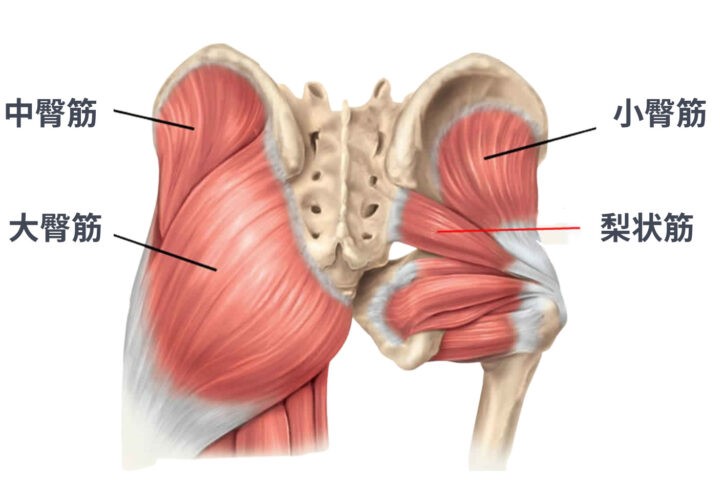

おしりの筋肉は、主に大臀筋・中臀筋・小臀筋という3つの筋肉で構成されています。

「全部まとめておしりの筋肉でしょ?」と思われがちですが、それぞれに役割の違いがあると言われています。骨盤や太ももの骨とつながり、体を安定させたり動かしたりする“土台”として働いているのが特徴です。

2. 大臀筋・中臀筋・小臀筋の位置と役割

まず大臀筋は、おしりの表面にある最も大きな筋肉です。立ち上がるときや階段を上る動作など、力を必要とする場面で使われる“パワー重視”の筋肉とされています。

次に中臀筋は、歩いているときに骨盤が左右に傾きすぎないよう支える役割があると言われています。

さらに小臀筋は、深い位置で股関節を細かく安定させるサポート役として働くと考えられています。

3つの筋肉がチームのように連携している、と捉えるとわかりやすいかもしれません。

3. 骨格との関係から見る筋肉の基礎知識

これらのおしりの筋肉は、骨盤と太ももの骨に付着しています。そのため、おしりの筋肉がうまく使われにくい状態になると、腰や股関節に負担がつながりやすいと言われています。